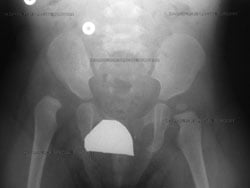

Anterior-to-posterior (front-to-back) preoperative X-ray of a dislocated right hip in toddler (shown at left).

In children, hip dysplasia more frequently affects the left hip than the right. About 80% of cases follow this pattern. The condition can, however, be present in both hips.